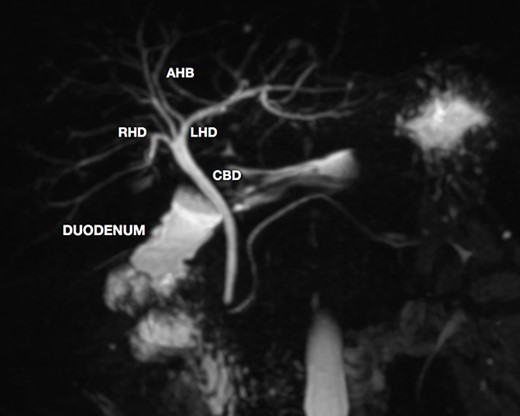

A magnetic resonance cholangiopancreatography (MRCP) confirmed the absence of gallbladder and of the cystic duct and artery (Figs 4–6). No other abdominal anomaly was identified.

MRCP showing biliary tract with GA and no other biliary anomaly; duodenum and the main pancreatic duct are also with visibility; AHB, anterior hepatic branch.